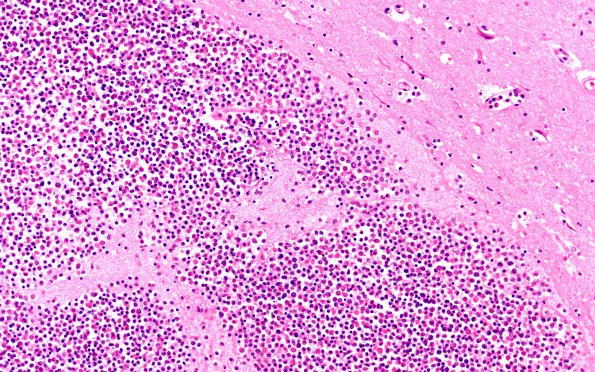

Washington University Experience | NEOPLASMS (HEMATOLYMPHOID) | Granulocytic Sarcoma | 4B2B Case 4F 20X

Multiple hemorrhages appreciated grossly in cerebral cortex and brainstem prove on microscopic examination to consist of a rim of fresh hemorrhage surrounding a pure collection of white cells most of which appear to be myeloblasts. These lesions have a predilection for the area of the grey-white junction